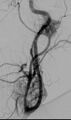

طرق العلاج الرئيسية هي الجراحة والانصمام[12] والعلاج الإشعاعي.[13]